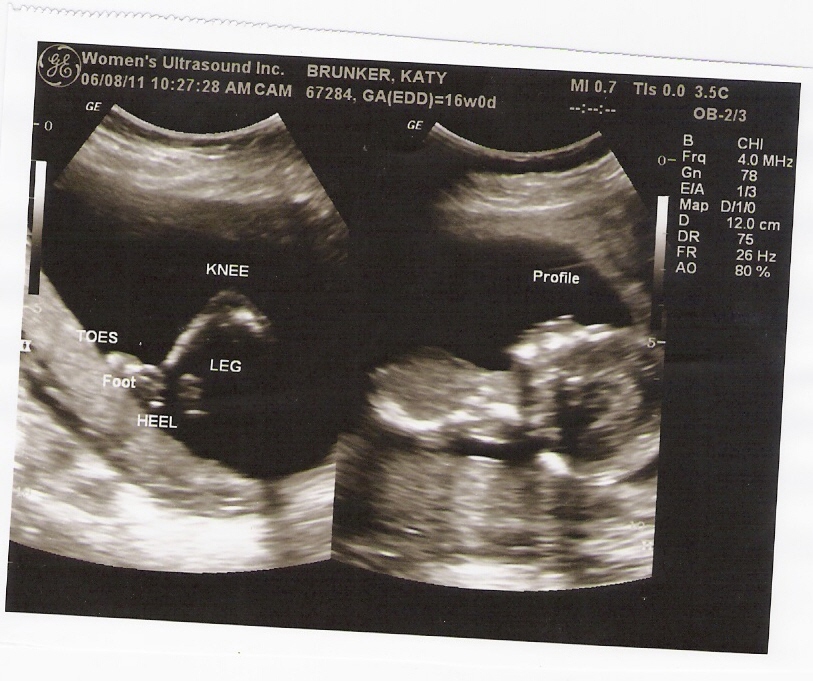

Favorite Moment This Week: getting to see the baby during the ultrasound on Wednesday. It is so amazing what you can see during the those. The spine was incredible during this one. The baby was stretching out, almost like it was trying to do a back bend and that is when the spine was easily seen. So amazing that all of this is going on inside of me. What an incredible miracle this is!

I feel like I rambled a lot above so I am going to stop tying and post some pictures of my growing belly and some ultrasound pictures of little nugget (this is what Ben and I call the baby)!! Enjoy!

| left side: profile and neck- right side: leg; hip, knee and foot |

| more leg and profile-amazing!! |